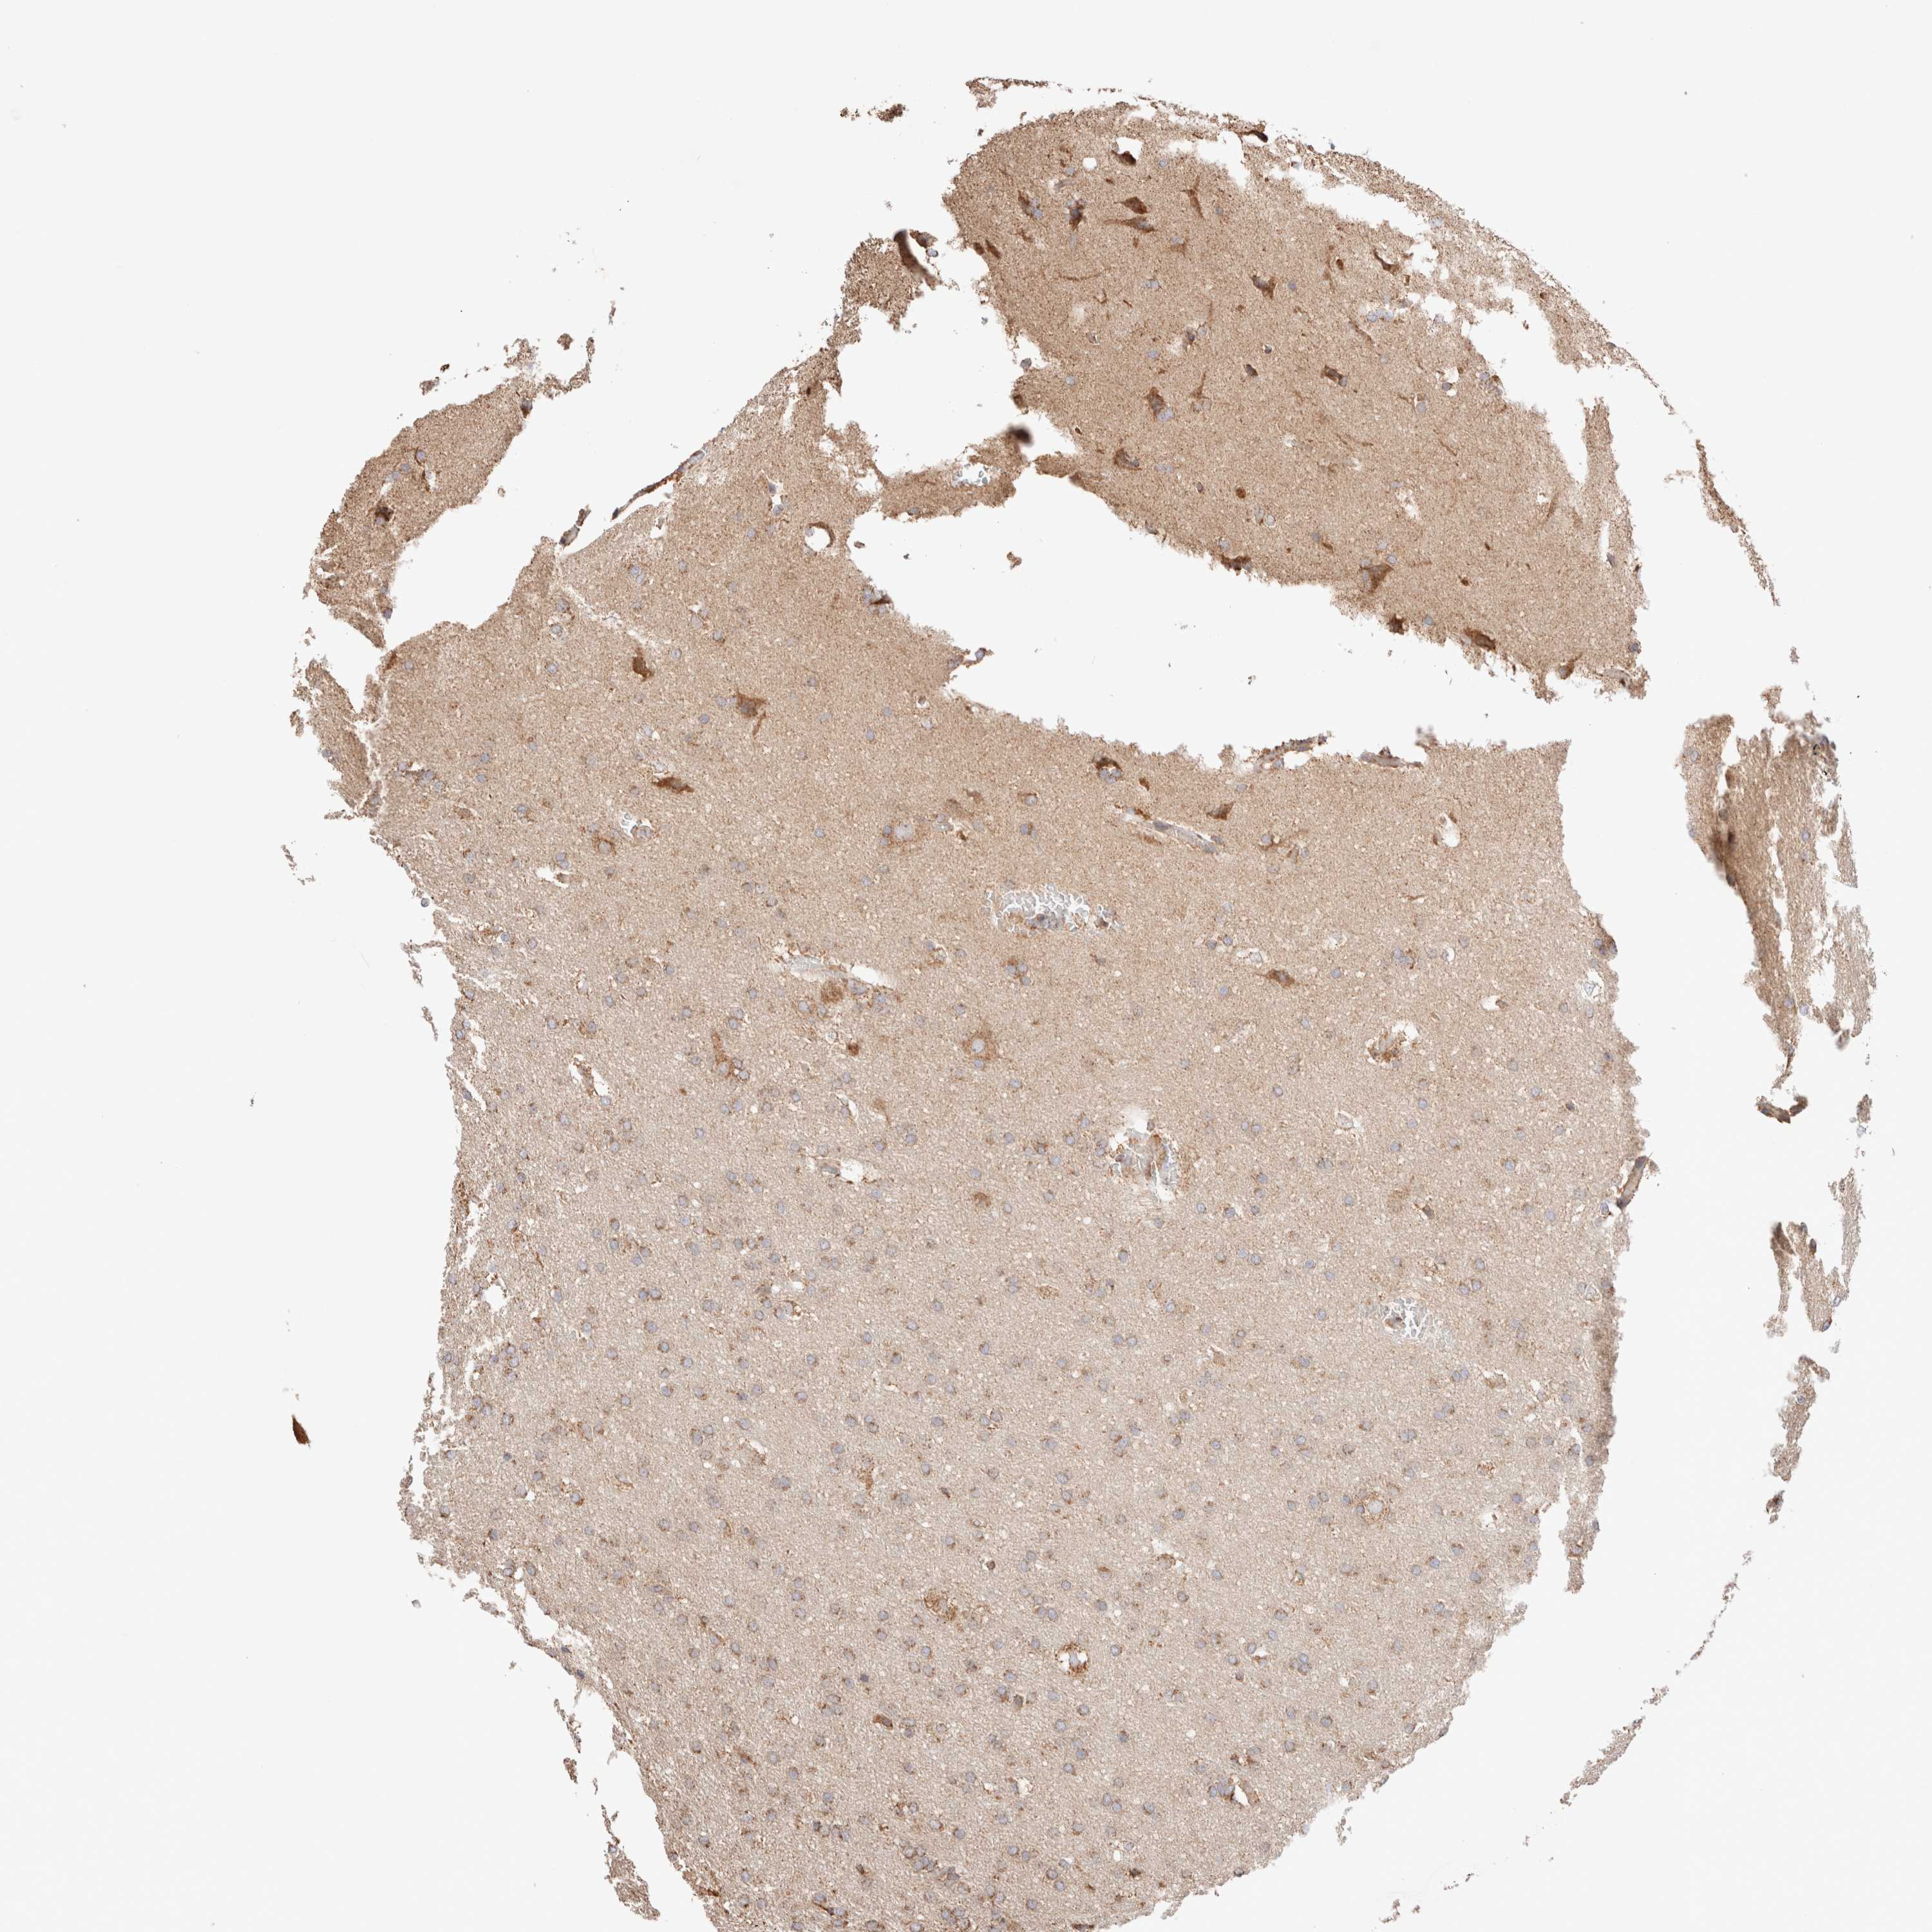

GLIOMA - Protein expressioni

A mouse-over function shows sample information and annotation data. Click on an image to view it in a full screen mode. Samples can be filtered based on level of antibody staining by selecting one or several of the following categories: high, medium, low and not detected. The assay and annotation is described here.

Note that samples used for immunohistochemistry by the Human Protein Atlas do not correspond to samples in the TCGA dataset.

Antibody stainingi

Antibody staining in the annotated cell types in the current human tissue is reported as not detected, low, medium, or high, based on conventional immunohistochemistry profiling in selected tissues. This score is based on the combination of the staining intensity and fraction of stained cells.

Each image is clickable and will lead to virtual microscopy that enables deeper exploration of all samples and also displays staining intensity scores, fraction scores and subcellular localization as well as patient and tissue information for each sample.

Antibody HPA027019

Staining

High

Medium

Low

Not detected

Intensity

Strong

Moderate

Weak

Negative

Quantity

>75%

75%-25%

<25%

None

Location

Nuclear

Cytoplasmic/membranous

Cytoplasmic/membranous,nuclear

Glioma, malignant, High grade

Glioma, malignant, Low grade